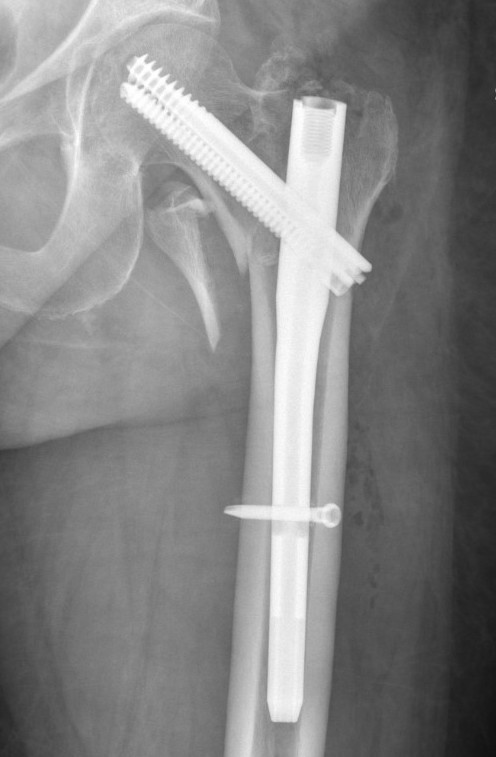

Cephalomedullary nail / Proximal femoral nail

Mechanical advantages

- load sharing rather than load bearing

- decreases lever arm

- supports medial cortex

Surgical advantages

- smaller incision / minimally invasive

- reduced blood loss

- shorter surgical times

Indications

- reverse oblique

- unstable fracture / loss of lateral buttress / loss posteromedial support

- subtrochanteric extension